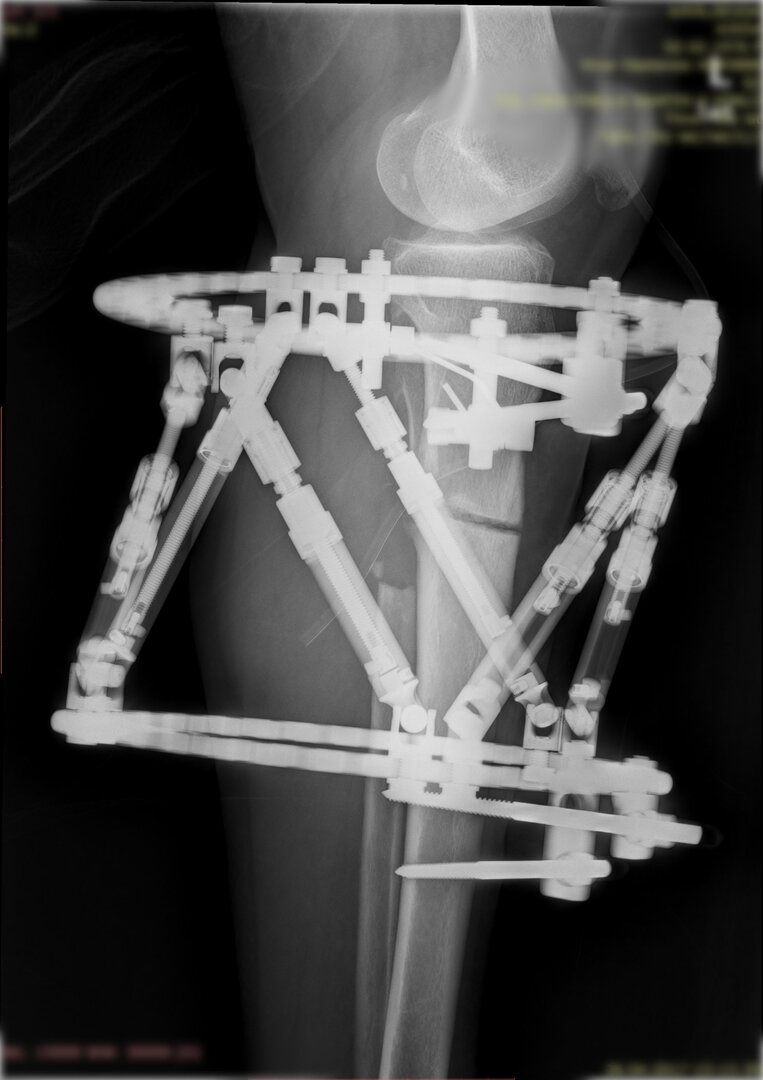

Deformitenin yeri ve miktarına bağlı olarak bilgisayar destekli sirküler eksternal fiksatör ile tedrici düzeltme yapılabilir. Bu sistemin avantajı düzeltme esnasında sistemle oynayarak yeni düzenlemeler yapmanıza izin vermesidir.

Bu ameliyat öncesi bir deformite analizi yapılıp hangi kemikte, normalden ne kadar sapma olduğu tespit edilir. Daha sonra bu kemiğe yine ostetomi yapılarak bu anormal sapma düzeltilir.  Bu düzeltme plak-vida veya intramedüller çivi ile akut olarak düzeltilebileceği gibi bilgisayar destekli sirküler eksternal fiksatör ile tedrici olarak ta yapılabilir. Hangi yöntemin hangi hasta için uygun olacağına hasta özelinde karar veriyoruz, ne tür cerrahi tedavi olması gerektiğini danışabilirsiniz.

Büyütmek için üzerine tıklayınız.